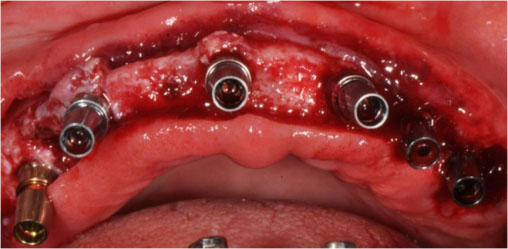

The patient agreed for fixed replacement of teeth and gave the consent for complex reconstruction for implant screw-retained prostheses for both the upper and lower arches. After four months of denture wearing and complete soft tissue healing, the dentures were duplicated in a surgical guide and the patient underwent a CBCT scan to decide optimal positions for implants in each arch. Six tissue-level implants (Myriad Connect, Equinoxmed Belgium) were placed in the mandible between the inter-foramina region (3.3/9.5 mm). The maxilla also had six implants between the maxillary sinus region (3.4/11; 2, 3.4/13; 2, 3.4/9.5;2, Xive Dentsply) (Figures 6 and 7). The retained second premolars of each arch were extracted during the surgery and replaced by implants. The patient had a waiting period of five months for prosthesis fabrication after surgery. The existing complete dentures were adjusted and relined several times to provide a perfect occlusion and oral hygiene was further evaluated every month.

japid-11-39-g006

Figure 6. Six implants in the mandible.

japid-11-39-g007

Figure 7. Six implants in the maxilla.